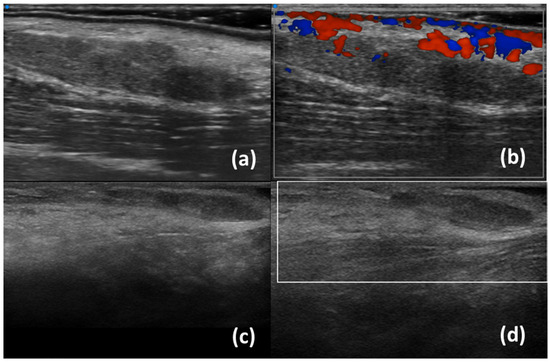

| Ferro et al. (2020) [35] | B-mode | SjD diagnostic value (SjD patients have higher inhomogeneity) Associations of inhomogeneity with Ro/SSA+ positivity Correlationsof inhomogenity with histological inflammation |

- Ferro, F.; Izzetti, R.; Vitali, S.; Aringhieri, G.; Fonzetti, S.; Donati, V.; Dini, V.; Mosca, M.; Gabriele, M.; Caramella, D.; et al. Ultra-high frequency ultrasonography of labial glands is a highly sensitive tool for the diagnosis of Sjögren’s syndrome: A preliminary study. Clin. Exp. Rheumatol. 2020, 38 (Suppl. S126), 210–215. [Google Scholar]

- Izzetti, R.; Fulvio, G.; Nisi, M.; Gennai, S.; Graziani, F. Reliability of OMERACT Scoring System in Ultra-High Frequency Ultrasonography of Minor Salivary Glands: Inter-Rater Agreement Study. J. Imaging 2022, 8, 111. [Google Scholar] [CrossRef]